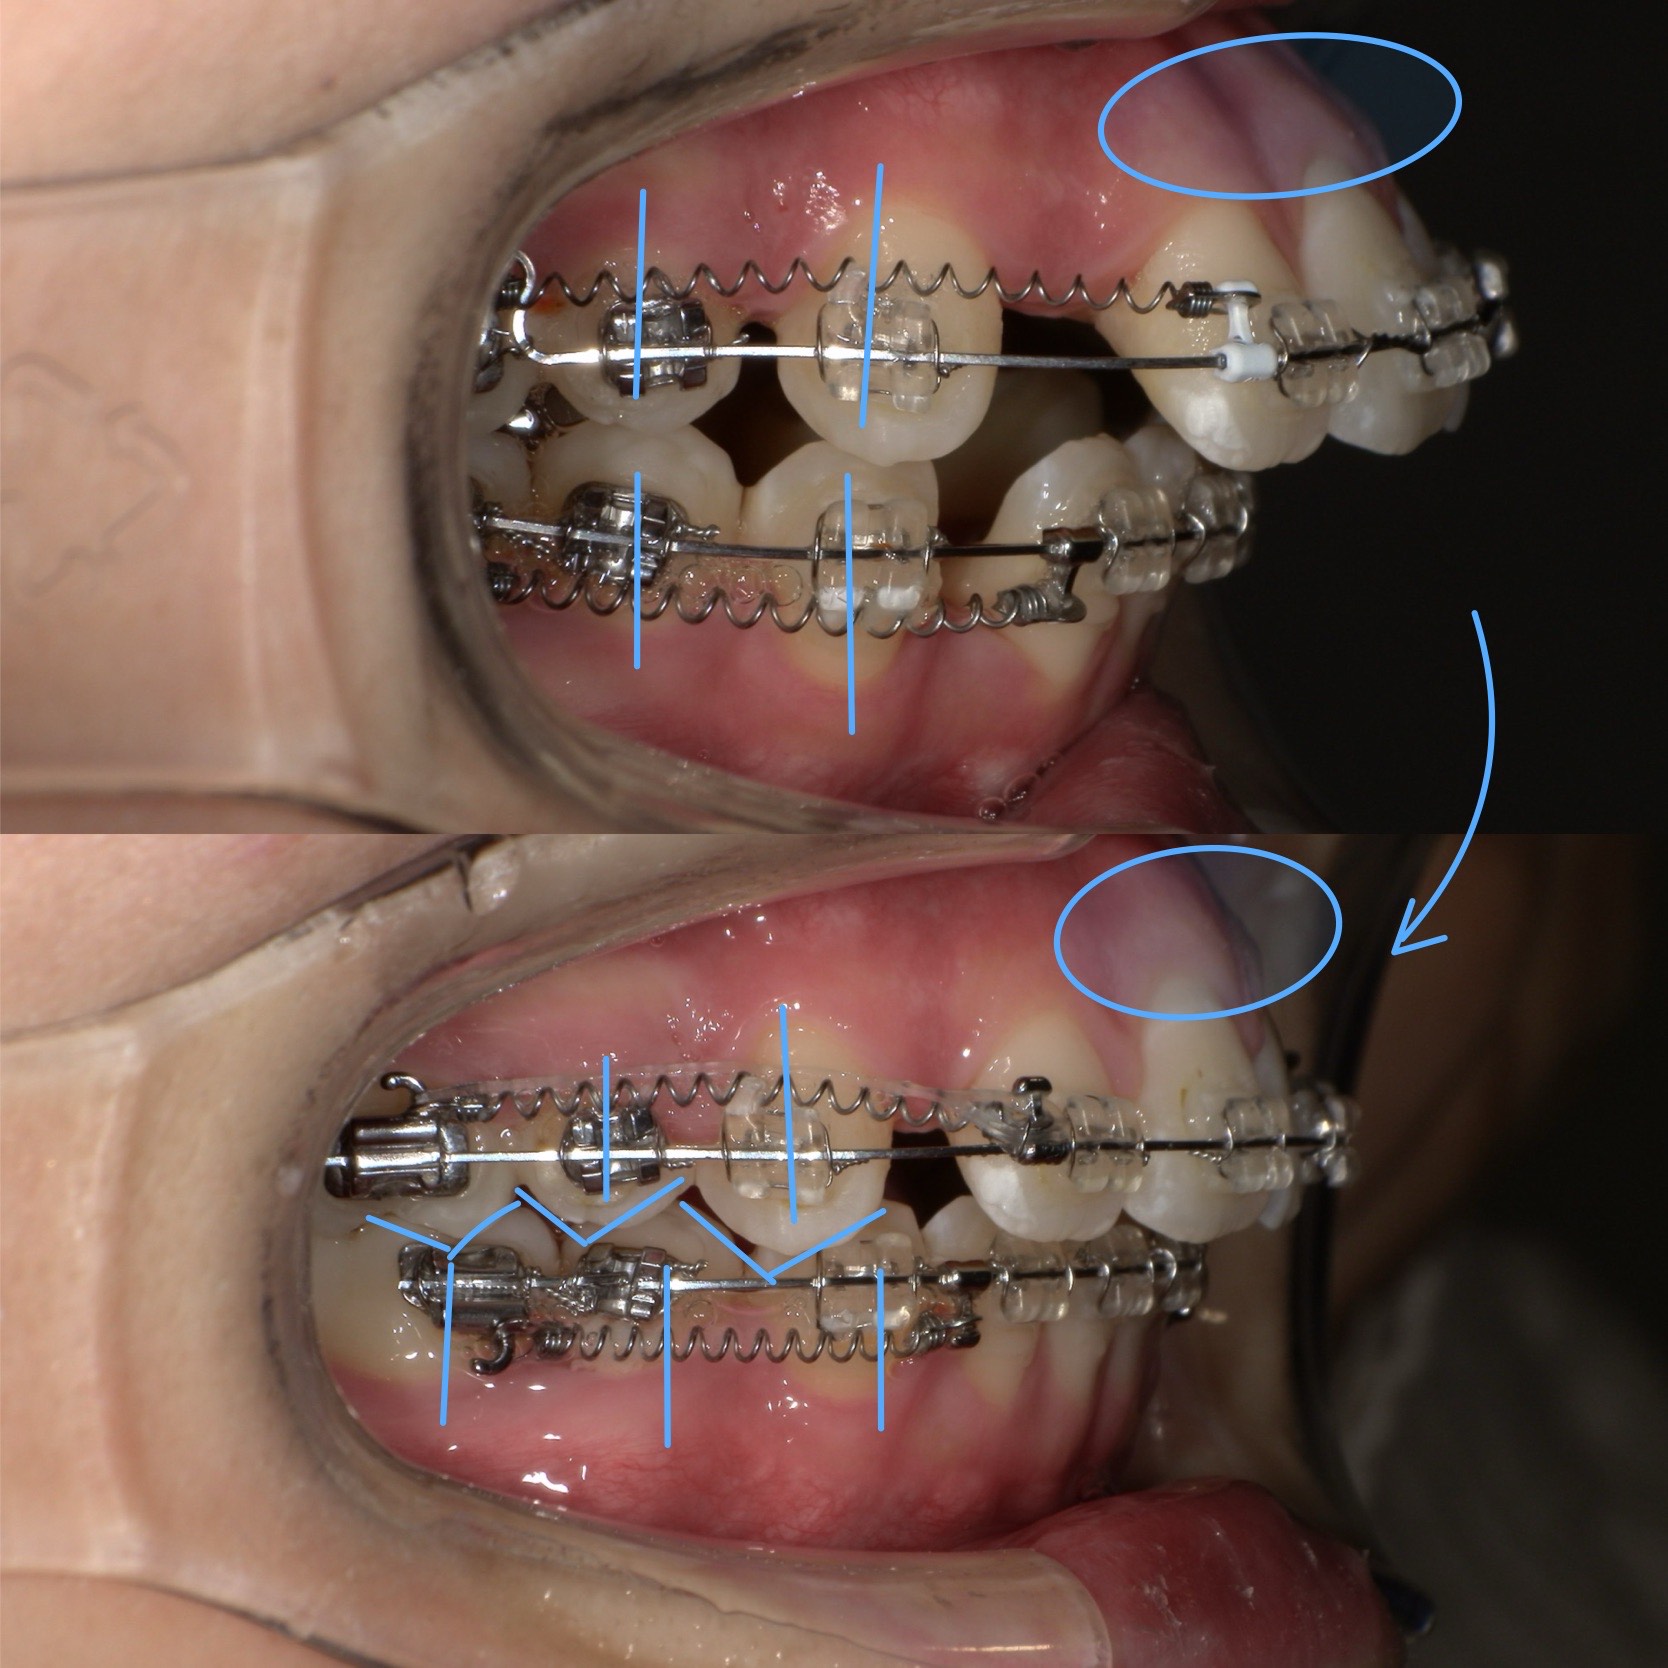

今回の写真は、

抜歯矯正約6ヶ月時点のリアルな変化。

まだ治療途中にも関わらず、

歯の並び・噛み合わせ・骨の前突傾向にはっきりとした改善が見られます。

今回の症例で起きている変化ポイント

写真を見ていただくと、

前歯の傾きが内側に入る

- 骨ごと歯が引っ込んでいる→口元も変化しています

- 噛み合わせのズレが改善方向へ→1本対1本で嚙んでいたのが1本対2本のかみ合わせへ